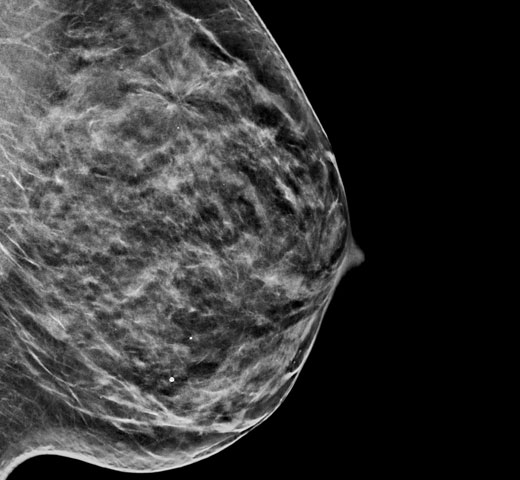

Superior accuracy for women with dense breasts compared to 2D alone.6

Clinical Images